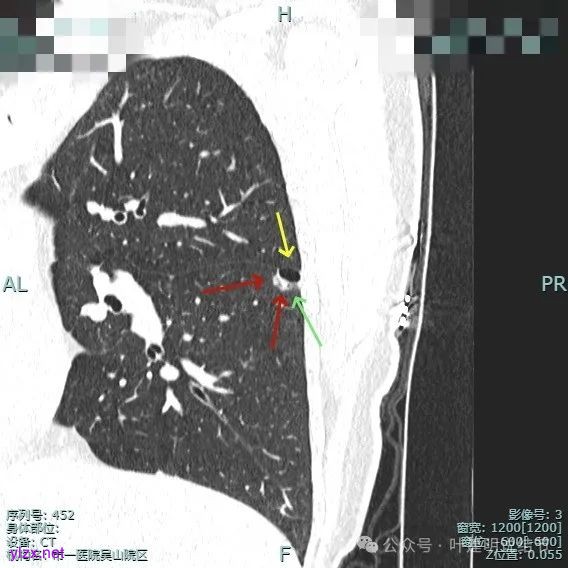

混合密度但还是太致密,内壁毛糙不平。

病灶轮廓清楚,囊壁厚薄不均,贴着叶间裂与胸膜。

1、诊断问题:这是很典型的囊腔型肺癌,符合我自己之前提出的囊腔型肺癌三要素:(1)囊壁厚薄不均;(2)血管进入囊壁;(3)囊腔内壁不光滑(或再加止整体轮廓与边界较清)。而且由于囊壁实性成分明显,所以是有风险的,要及时干预处理。